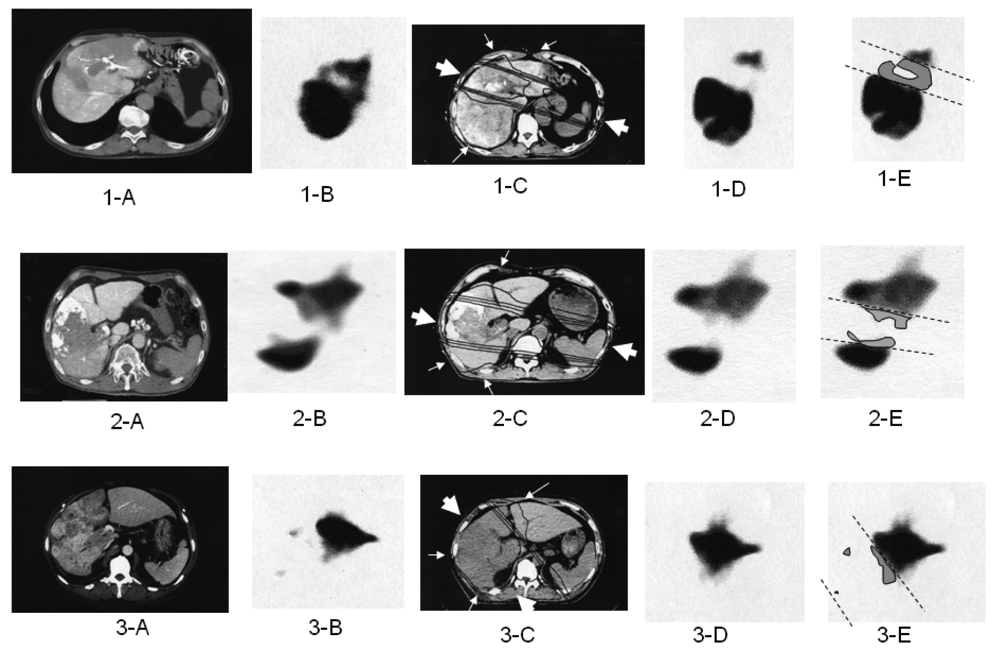

The optimal 3DCRT beam directions (optimal angles of the gantry) were explored using the SPECT images (Figure 2; 1-B, 2-B, 3-B) for guidance. The directions of the two high-dose beams were designed to cover primarily the main tumor and PVTT, and to irradiate FLV as little as possible. As shown in Figure 1, the doses of the high-dose beams were limited to 38.25 Gy/18 fractions/4 weeks to prevent adverse effects to the duodenum, spinal cord, and kidneys [9,10]. Three additional low-dose beams of 6.75 Gy/18 fractions/4 weeks were required to elevate the dose to the CTV, resulting in a total dose of 45 Gy to the isocenter [11]. These low-dose beams were designed to avoid irradiating risk organs such as the stomach, duodenum, and spinal cord. Doses of 2.25 Gy for each additional beam do not cause liver damage even if the beams irradiate FLV. In terms of the kidney, the volume irradiated at 20 Gy or more was planned to not exceed 30% of the total volume. Finally, the couch angle was adjusted to the maximum limit of 90°.

2.5. Follow-up Evaluation

2.8. Estimation of RIDFLV and Destruction Ratio

We previously reported the occurrence of RIDFLV after RT [3,4]. The presence of RIDFLV was confirmed in all patients who received follow-up SPECT. In the present study, we performed quantitative analysis of RIDFLV. Namely, as illustrated in Figure 2, the follow-up SPECT images (Figure 2, 1-D, 2-D, 3-D) were fused with the corresponding simulation CT images (Figure 2, 1-C, 2-C, 3-C) and the image data were input to the RT planning computer. Because the simulation CT images included the SPECT image prior to RT, RIDFL was outlined by subtracting the SPECT image obtained after RT from that prior to RT (Figure 2, 1-E, 2-E, 3-E) and RIDFLV was calculated using the data of all slices; this value was then used to calculate the destruction ratio as follows: Destruction Ratio = RIDFLV/FLV × 100 (%). RIDFLV and the destruction ratio are outcome factors rather than predictive factors, and thus cannot be used prior to RT to predict liver damage.

We then explored predictive factors of liver damage caused by RT, based on the finding that the borderline (dashed lines in subfigures E in Figure 2) between RIDFL and the remaining FL after 3DCRT is almost linear, and that the four iso-dose curves on the simulation CT are also linear, and almost correspond with the outer line of the high-dose beam. Therefore, the predictive factors of liver damage caused by RT for (X) Gy could be determined by calculating the relationship of the iso-dose curve to the dashed line, as FLVXGy = RIDFLV/FLV × 100 (%). We fused the simulation CT and the follow-up SPECT to determine which Gy isodose curve was coincident with the dashed line.

Figure 2E shows the relation of the boundary lines between RIDFLV and FLV (dotted lines) to the four iso-dose lines from simulation CT and SPECT after 3DCRT (Figures 2C and 2D). In all patients, the boundary lines passed through the midspace between the 20 and 30 Gy isodose curves, in each slice.